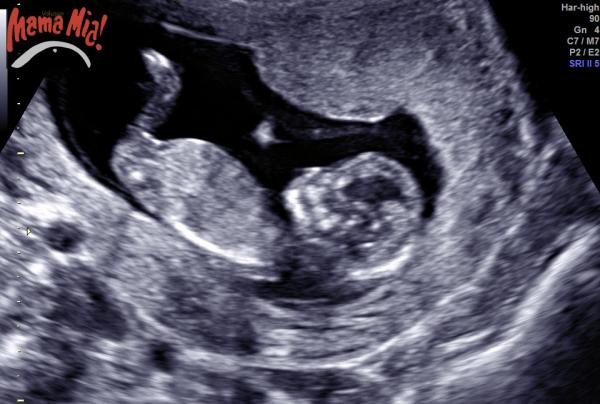

Idag har min värld rasat samman. Vid RUL i morse upptäckte man att min flicka har hydronefros, vidgat njurbäcken, någon vars barn haft det? Om det "bara" hade varit det hade jag varit relativt lugn om än aningens ledsen. BM hittade även något knas på hjärtat och jag fick en tid för UL imorgon bitti på ett större sjukhus av specialistläkare. Jävla skit ![]()